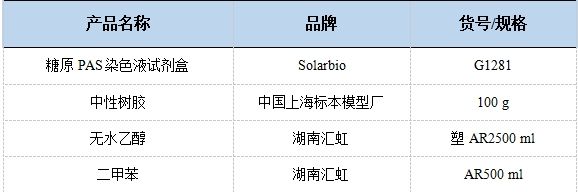

五、實驗材料

2.主要試劑